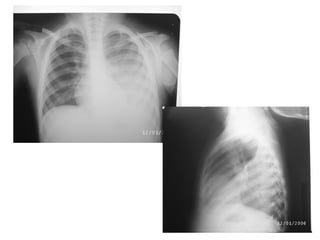

Manifestações radiográficas

Pneumonia por Mycoplasma, sorologia positiva

Radiografia  Não precisaser feita na criança tratada em casa.  Radiografias em perfil não precisam ser feitas rotineiramente, em todos os casos.  A imagem radiológica não distingue etiologia viral ou bacteriana.  Não se recomenda radiografias de controle, exceto para pneumonias complicadas, como com derrame pleural ou atelectasia.

Pneumonia por Mycoplasma,sorologia positiva